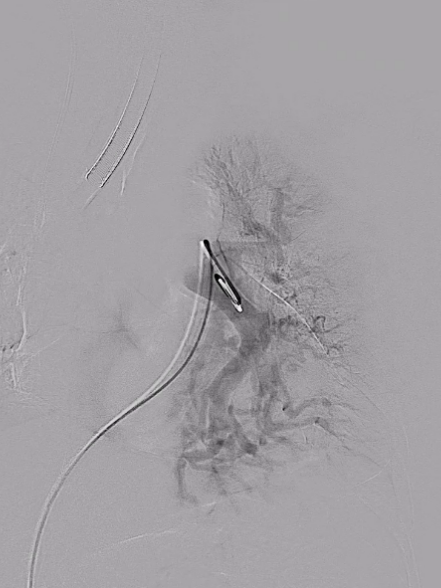

手术过程:

血管外科团队顺利完成股静脉穿刺,置管造影,然后在DSA指引下顺利送入抽吸导管至左右肺动脉主干,以取栓系统取出大量新鲜、陈旧混杂血栓,双肺末梢动脉即刻恢复灌注。

右肺取栓前后影像